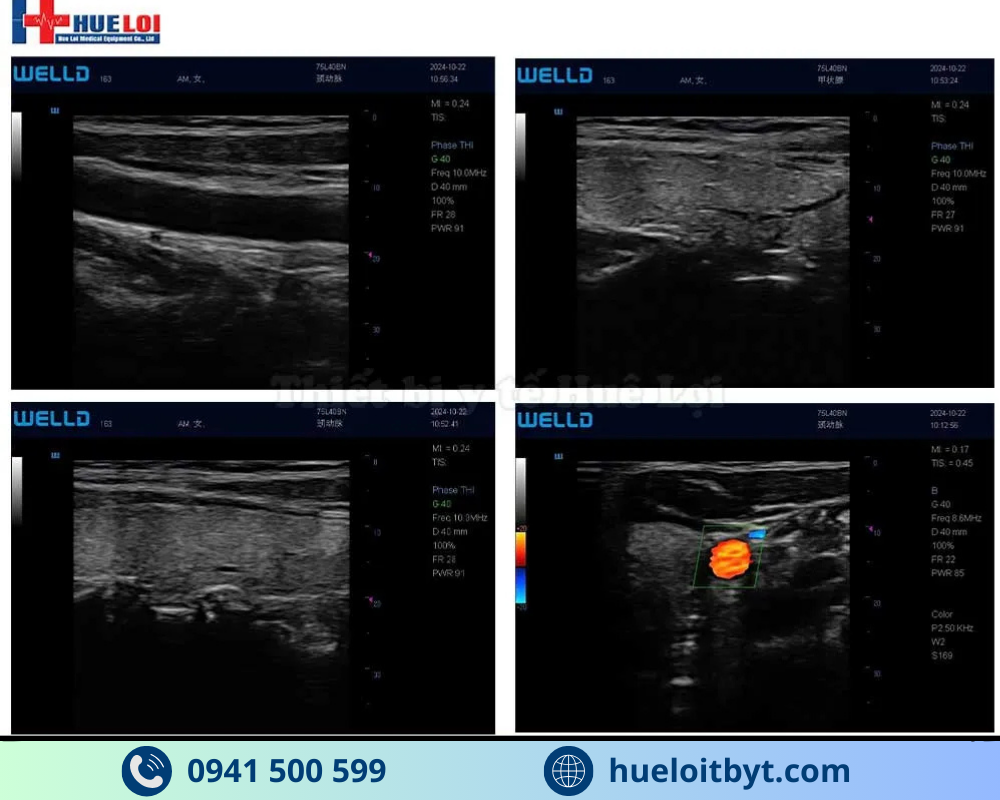

Máy siêu âm xách tay cảm ứng P10 là mẫu máy siêu âm xách tay Doppler màu hiện đại, chất lượng hình ảnh 2D vượt trội hơn hẳn so với các máy siêu âm khác trong phân khúc cơ bản. Với P10, toàn bộ các phím chức năng và các thao tác khi siêu âm sẽ được tích hợp và sử dụng dễ dàng trên màn hình cảm ứng 12.1”. Máy có thiết kế nhỏ gọn, trọng lượng chỉ 1.65kg, thuận tiện cho các bác sĩ mang theo và thăm khám tại nhà bệnh nhân.

Độ sâu tối đa của chế độ Doppler màu (mm) |

≥40 |

≥90 |

|

Độ sâu thăm dò Doppler phổ (mm) |

≥40 |

≥80 |